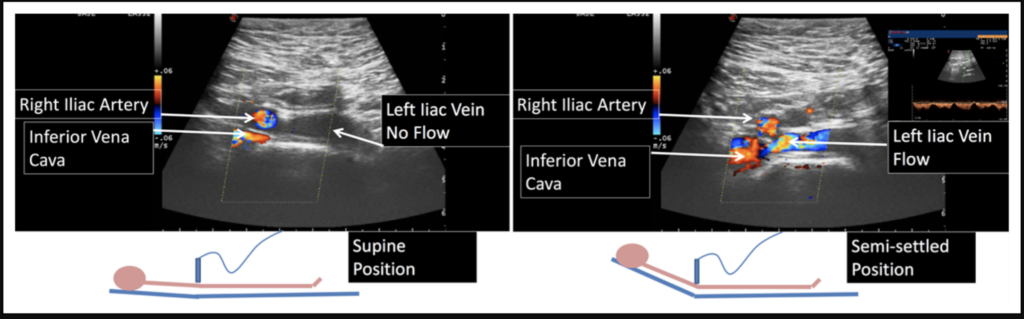

Many of these 'compressions' simply disappear when the patient sits up.

In a similar way, our understanding of iliac vein compression may also be influenced by how and when we observe it.

Most imaging studies—CT or MR venography—are performed with the patient in a supine position. What we see, therefore, reflects a single moment under specific conditions.

However, venous physiology is dynamic. When patients are upright or sitting, the relationship between anatomical structures and venous flow may change. In some cases, the degree of compression appears less pronounced, or functionally less significant.